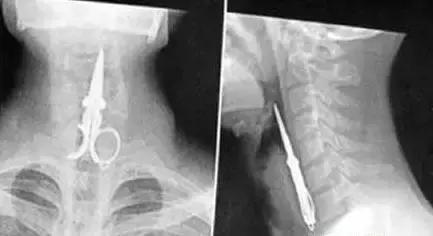

▲卡在喉咙里的剪刀(真是艺高人胆大)